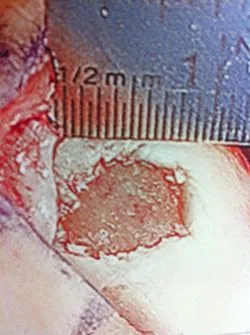

Pics of nodules removed during scope.  A separate incision had to be made to remove the nodules due to the size.

Measuring the size and depth of the OCD.